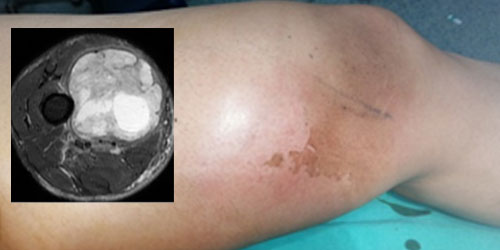

Liposarkom

Kötü huylu yumuşak doku tümörleri arasında ikinci sıklıktadır. Nedeni tam olarak bilinmemektedir. Çok farklı yaşlarda görülebilir fakat sıklıkla 40 yaş sonrası ortaya çıkar.